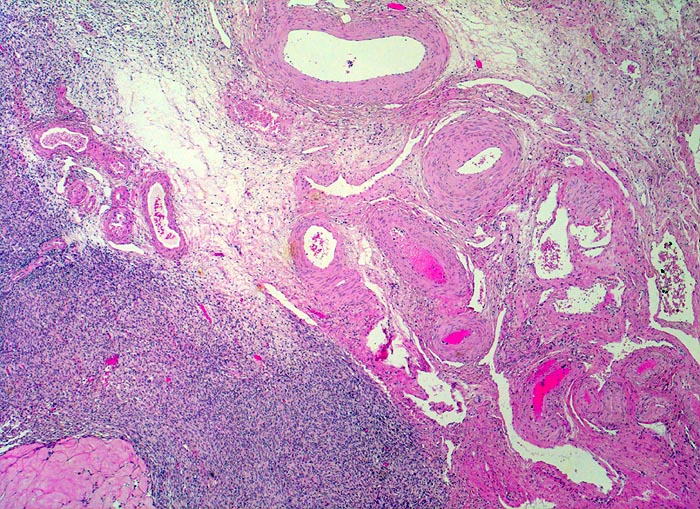

PathoPic ID 4284 - normales Ovar: Hilus

normales Ovar: Hilus

Ovar

Genitalorgane, weiblich

Rechts oben im Bild zahlreiche dickwandige Gefässe des Ovarhilus in lockerem Stroma eingebettet. Links unten im Bild Anschnitt eines Corpus albicans.

Histologie

25